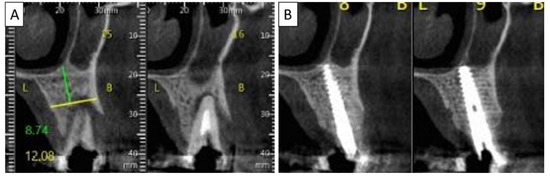

Figure 9.

(A) Panoramic CBCT section shows associated apical radiolucency of tooth 15. (B) Coronal CBCT section shows tooth 15 with vertical root fracture and destroyed buccal bony wall and intact palatine. (C) Panoramic CBCT section shows bone formation around the implant in area 15. The coronal CBCT section shows the implant placed in the region of tooth 15.